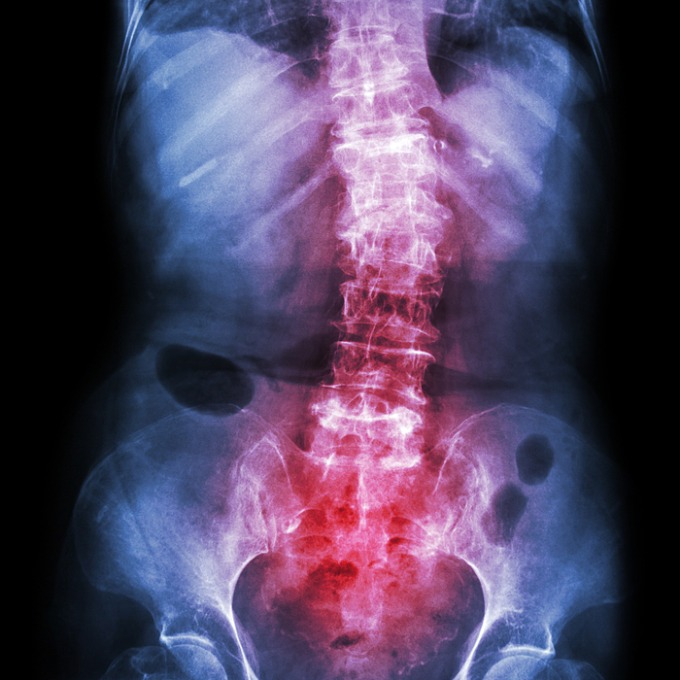

Đau lưng kiểu viêm là triệu chứng đặc trưng của viêm cột sống dính khớp. Ảnh: Shutterstock